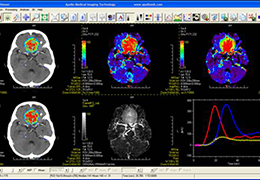

ANYTHINK 经导管主动脉瓣膜置换术分析系统